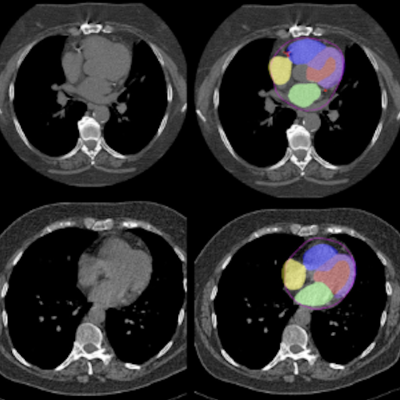

AI is applied to CT scans to automatically segment different heart chambers and quantify arterial plaque. Non-contrast CT slices (left) with superimposed segmentations (right). One model segments CAC (shown in red) while another model segments the four different heart chambers (shown in yellow, blue, purple, and green). Credit: Slomka laboratory/Nature Communications; see licensing information below.

The researchers combined two previously validated algorithms—one developed by Slomka and colleagues that measures CAC, and another that can segment cardiac chamber volumes—to analyze routine chest CT scans (i.e., low-dose scans with no contrast and no gating). They evaluated scans from 24,354 patients who had CT performed as part of the National Lung Screening Trial and identified several cardiac factors that were associated with an increased risk of death, such as a large amount of CAC and increased mass or volume of specific heart chambers. What’s more, the researchers found that combining all the factors together (including clinical data like age and medical history) was a better predictor of death than any one factor alone.